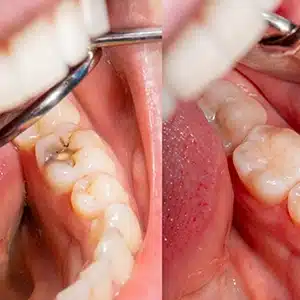

2. Removing the Decay

Once the area is numb, your dentist will use specialized dental tools to carefully remove the decayed or damaged part of the tooth. This step is crucial to prevent further deterioration and create a clean, bacteria-free surface, ensuring the filling bonds properly for long-term durability.

3. Placing the Filling

After removing the decay, your dentist will thoroughly clean and prepare the cavity for the filling. The chosen filling material is applied in layers, shaped to match the tooth’s natural contours, and hardened using a curing light (for composite fillings). This process restores strength and function.